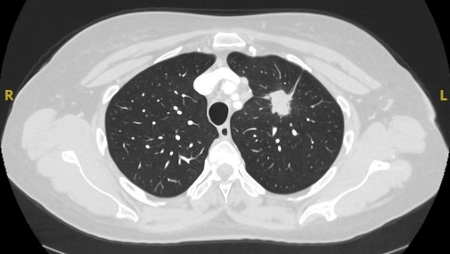

Semi-solid nodules: growth of the solid component suggests that further investigation and/or treatment should be considered.[Figure caption and citation for the preceding image starts]: Computed tomography (CT) sections with examples of semi-solid solitary nodulesFrom the collection of Dr George Tsaknis, MD, PhD, FRCP(London), MRQA, MAcadMEd, PGCert; used with permission [Citation ends].